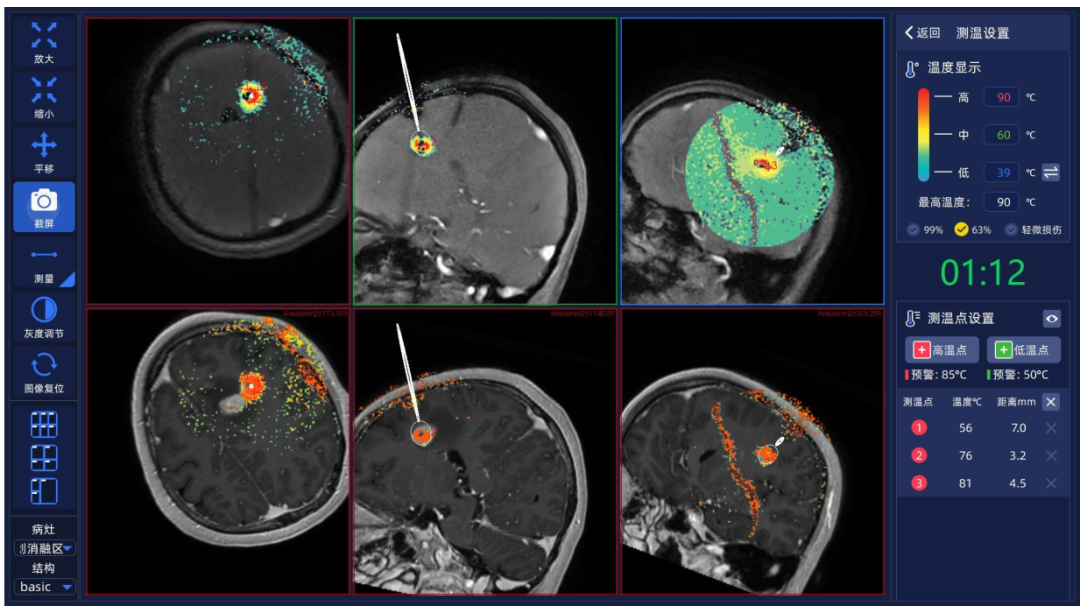

患者为52岁女性,因“头痛伴恶心10余天”入院。根据患者术前影像学及神经系统查体,病变主要位于左额叶内侧,累及胼胝体膝部及侧脑室壁,考虑胶质瘤可能。肿瘤位置深在,多中心且不规则,位于重要功能区,开颅手术切除困难,并发症发生率高。经与患者家属充分沟通、科室讨论后决定采用磁共振引导激光消融术。王宏伟团队首先对患者颅内病变行机器人辅助下立体定向活检,术中快速病理报告提示该病变为胶质瘤伴坏死,随后在机器人导航辅助下,王宏伟团队通过微创切口将两根激光光纤分别精准置入颅内肿瘤靶点。在术中磁共振的实时温度监控下,进行肿瘤精确热凝损毁,利用双波长消融优势,先采用980nm波长激光进行初步消融,迅速形成清晰消融区域,并在此基础上切换为1064nm波长扩大消融区域,随后退针两次,完成不规则病灶中部和尾部的消融;而较小病灶则在1064nm波长激光的热效应作用下实现一次消融。消融后半小时即行术中MRI检查,显示清晰消融边界,基本覆盖原肿瘤强化灶范围。肿瘤消融范围理想,患者术后恢复良好,复查颅脑CT无明显出血,术后6天顺利出院。患者术后病理诊断为胶质母细胞瘤,后续继续进行相关辅助治疗及随访。

术中MRI实时监测下颅内肿瘤激光消融范围